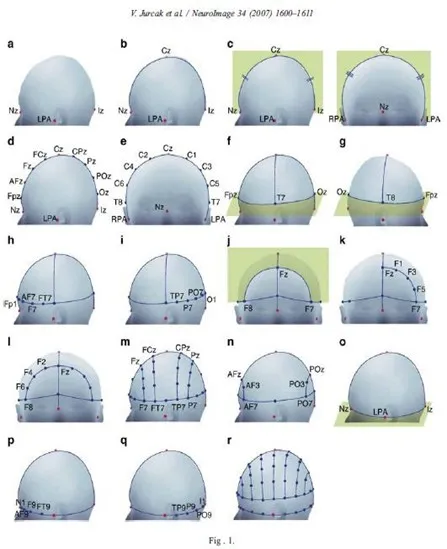

The first measurement is in the anterior-posterior plane through the vertex, taken from the nasion to the inion. This measurement is divided into 5 separate areas (see fig.1).

The first mark is placed at 10% of the total measurement and labeled Fp. The second, third, fourth and fifth marks are placed at 20% intervals of the total measurement and labeled F, C, P, and O. Note that the O mark would be located at 10% of the measurement above the inion. The expression Fp, F, C, P and O represent the fronto polar, frontal, central, parietal and occipital areas, respectively.

Lateral measurement of the central coronal plane strats at the left preauricular point thrugh the C vertex mark to the right preauricular point (fig.2). A mark is placed at 10% of this measurement over the preauricular points and labeled T.

The expression T represents the temporal area. Marks are then located at 20% of the lateral measurement and labeled left and right C, and the C vertex location is crossed.

A circumferential measurement (fig.3) is then taken over the temporal lobes from the midline Fp position to the midline O position.

A mark is made at 10% of this measurement indicating the left or right Fp electrode position. Marks are then made at 20% of the measurement and are labeled inferior frontal, mid-temporal, and posterior temporal and left or right occipital (note that the mid-temporal electrode positions are crossed). The remaining 10% measurement from the left and right occipital marks would be the midline = position. Variations of this measurement have been described by Harner and Sannit (1974)

Fig.1 Lateral view oof skull to show methods of measurement from nasion to inion at the midline. Fp is frontal pole position, F is the frontal line of electrodes, C is the central line of electrodes, P is the parietal line of electrodes and O is the occipital line. Percentages indicated represent proportions of the measured distance from the nasion to the inion. Note that the central line is 50% of this distance. The frontal pole and occipital electrodes are 10% from the nasion and inion, respectively. Twice this distance, or 20% separates the other lines of electrodes

Fig.2 Frontal view of the skull showing the method of measurement for the central line of electrodes as described in the text.

Fig.3 Superior view with cross section of skull through the temporal line of electrodes illustrating the 10-20 system applied in this direction as described in the text

Antero-posterior measurements are taken from the left and right Fp position through the lateral C position to the left and right O position. This measurement is then divided equally by 25% marks and labeled lateral F, lateral C, and lateral P. Anterior coronal measurements are taken from the left and right inferior frontal position through the midline F position and divided into 25% segments, making crosses at the left lateral frontal, F vertex and right lateral frontal positions. A posterior coronal measurement is taken from the left posterior temporal mark through the midline P position and this is also divided into 25% segments and marks are labeled left lateral P, midline P and right lateral P (fig.4)